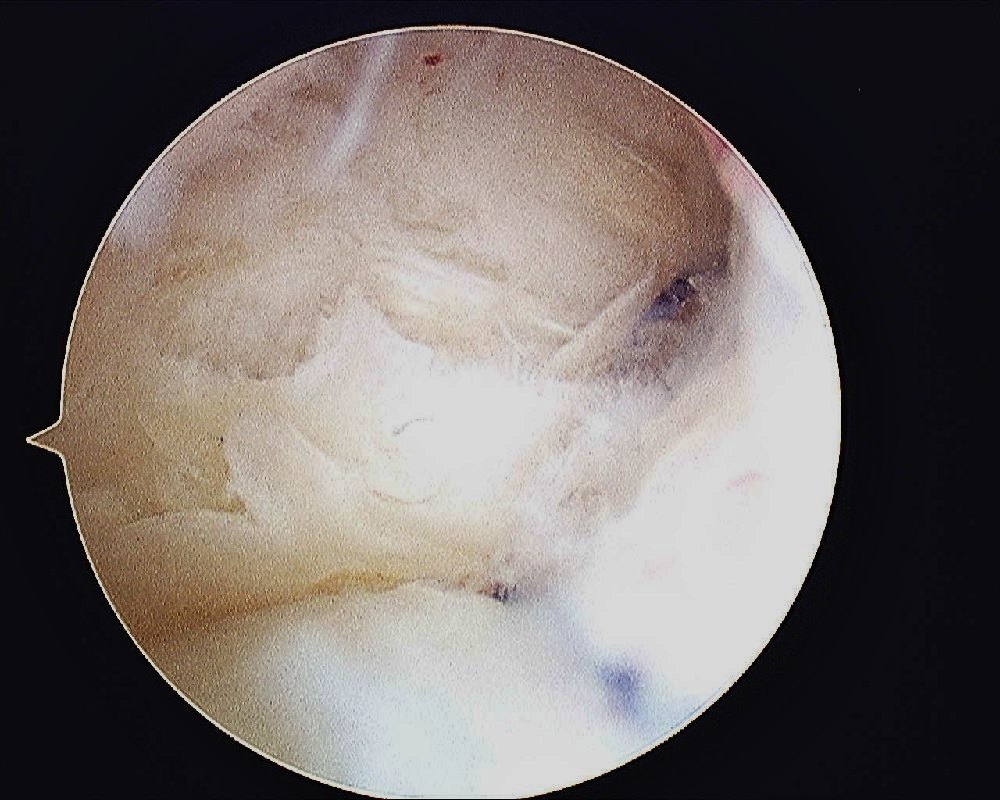

- TFCC Tear – Palmer Type IB

A PDS 3/0 suture is passed into the joint and retrieved through the 4/5 portal using a small arthroscopic grasper

The cannula is passed into the joint again to pass a suture shuttle. I use the PDS 3/0 as a suture shuttle.

The 1st PDS suture that was passed through the TFCC is shuttled back into the joint and out of the capsule.